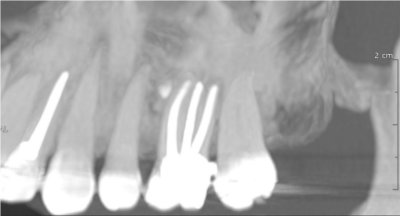

Images de panoramiques dentaire:

SCANNER DENTAIRE (DENTALSCANNER)

Les nouvelles générations de scanner permettent de faire une acquisition d’un volume global d’une partie du corps et de travailler à l’intérieur de ce volume en isolant une structure anatomique donnée et de l’explorer dans tous les plans de l’espace.

Grace à la technique de seuillage il est possible de dissocier progressivement les dents des structures osseuses environnantes dans le volume donné.